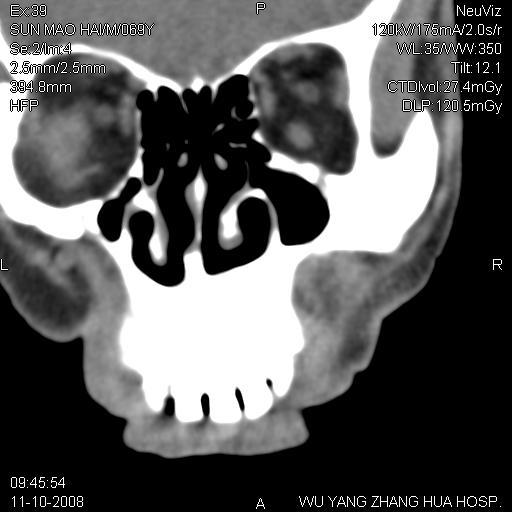

标题: CT16568:右面部瘘管半年余,无其它不适. [打印本页]

标题: CT16568:右面部瘘管半年余,无其它不适.

考虑右上颌异位齿(或斜向阻生齿)并根尖脓肿。

1.右上颌异位齿

2.右上颌化脓性骨髓炎

3.右下鼻甲肥大

支持三楼意见。(这种长法还真少见,再长再尖点就成獠牙了。)